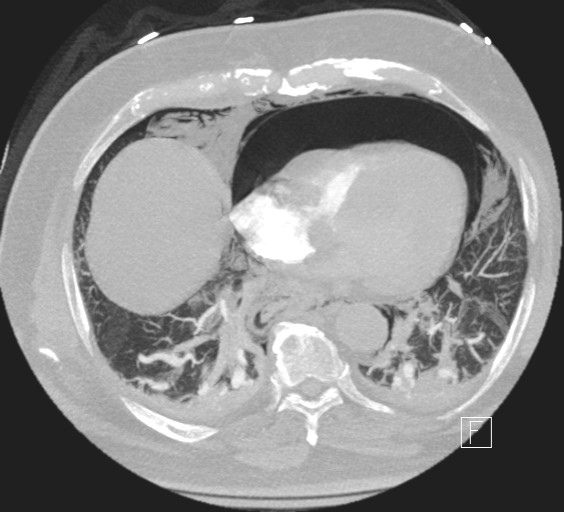

Figure 3. Patient’s CT scan.

A 72-year-old gentleman with achalasia who weighed 91 kg was admitted for an elective POEM procedure (Figure 1). The procedure started with stable hemodynamics on a constant ventilator setting of respiratory rate of 10-16/hr; tidal volume of 443; positive end-expiratory pressure (PEEP) of 5 cm H2O; positive inspiratory pressure of 22-24; end tidal carbon dioxide of 28; arterial oxygen saturation of 100. However, 45 minutes into the procedure, the patient went into pulseless electrical arrest. The scope was withdrawn, and he was revived after 10 minutes of cardiopulmonary resuscitation. The procedure was aborted and he was transferred to the ICU intubated, critically ill, and on escalating doses of epinephrine and norepinephrine. Follow-up diagnostic imaging (Figures 2 and 3) showed a small heart with air tracking around it, the mediastinum, the esophagus, and the aorta, confirming tension pneumomediastinum.